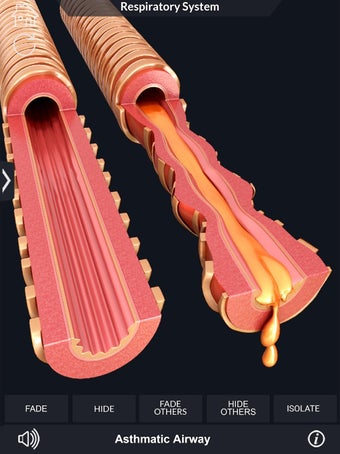

呼吸器系の解剖学は、肺、気管、およびすべての気道を含む呼吸器系の解剖学の研究です。最も一般的なアプローチは、系を上部と下部に分割することです。上部には気管、主気管支、および終末および前頸気道が含まれます。下部には肺と最小の大きさの末梢気道が含まれます。これらの部分それぞれには特徴的な外観と機能があります。

このアプリケーションは、高度にリアルな呼吸器系のモデルです。ユーザーは任意の角度および任意の平面から呼吸器系の解剖学を表示できます。ユーザーは360°回転し、ズームインおよびズームアウトして解剖学をよりよく研究することができます。ユーザーはまた、画面に描画するためのさまざまなツールを使用して写真を撮ることもできます。